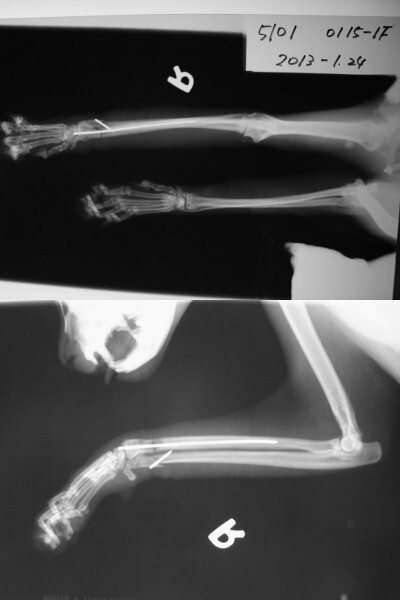

主題: 高雄 鳳山區 五福一路 老鼠夾貓咪 申請者姓名: 劉雅雲 花色: 申請日期: 2013-03-01 09:58:05 申請者部落格: 申請者臉書網址: 所在縣市/合作醫院: 高雄市/樂生動物醫院 治療費用: 18300元 需求人數: 19人 已結案 (2013-06-27 14:21:29) 報名人員: Yi-Jing Wang(已付款)、Luna Tsai(已付款)、Phyllis Chan(已付款)、雲之凡 x2(已付款)、Ray Chen(已付款)、Cay Way(已付款)、Li Li Hsieh(已付款)、王鼎方 x2、betty huang(已付款)、KAYU、謝欣蓓(已付款)、謝立立(已付款)、以四面佛名義迴向阿咪、咪仔 x5(已付款)、chiawei(已付款)、Emily Chou x2(已付款)、 候補人員: 動物病情說明: 1/15志工版裡的求援案件,被老鼠夾夾到的貓咪在地方拖行, 被好幾位民眾合力打開老鼠夾之後貓咪緊張躲到二樓的遮陽棚快4天沒下來吃東西, 後來到民眾二樓開窗去放誘捕籠抓到貓咪就醫. 醫生到院幫貓咪拍X光, 因為有骨折, 採用內固定法手術, 貓咪到院因為已經有化膿,所以留至院中治療, 恢復時間會較長.

明細如下:

血液生化及電解質 1500

X光片 300*6 = 1800

內固定法手術 6000

住院治療 300*30=9000<1/15 - 2/27> 醫生只算30天費用

Total: 18300